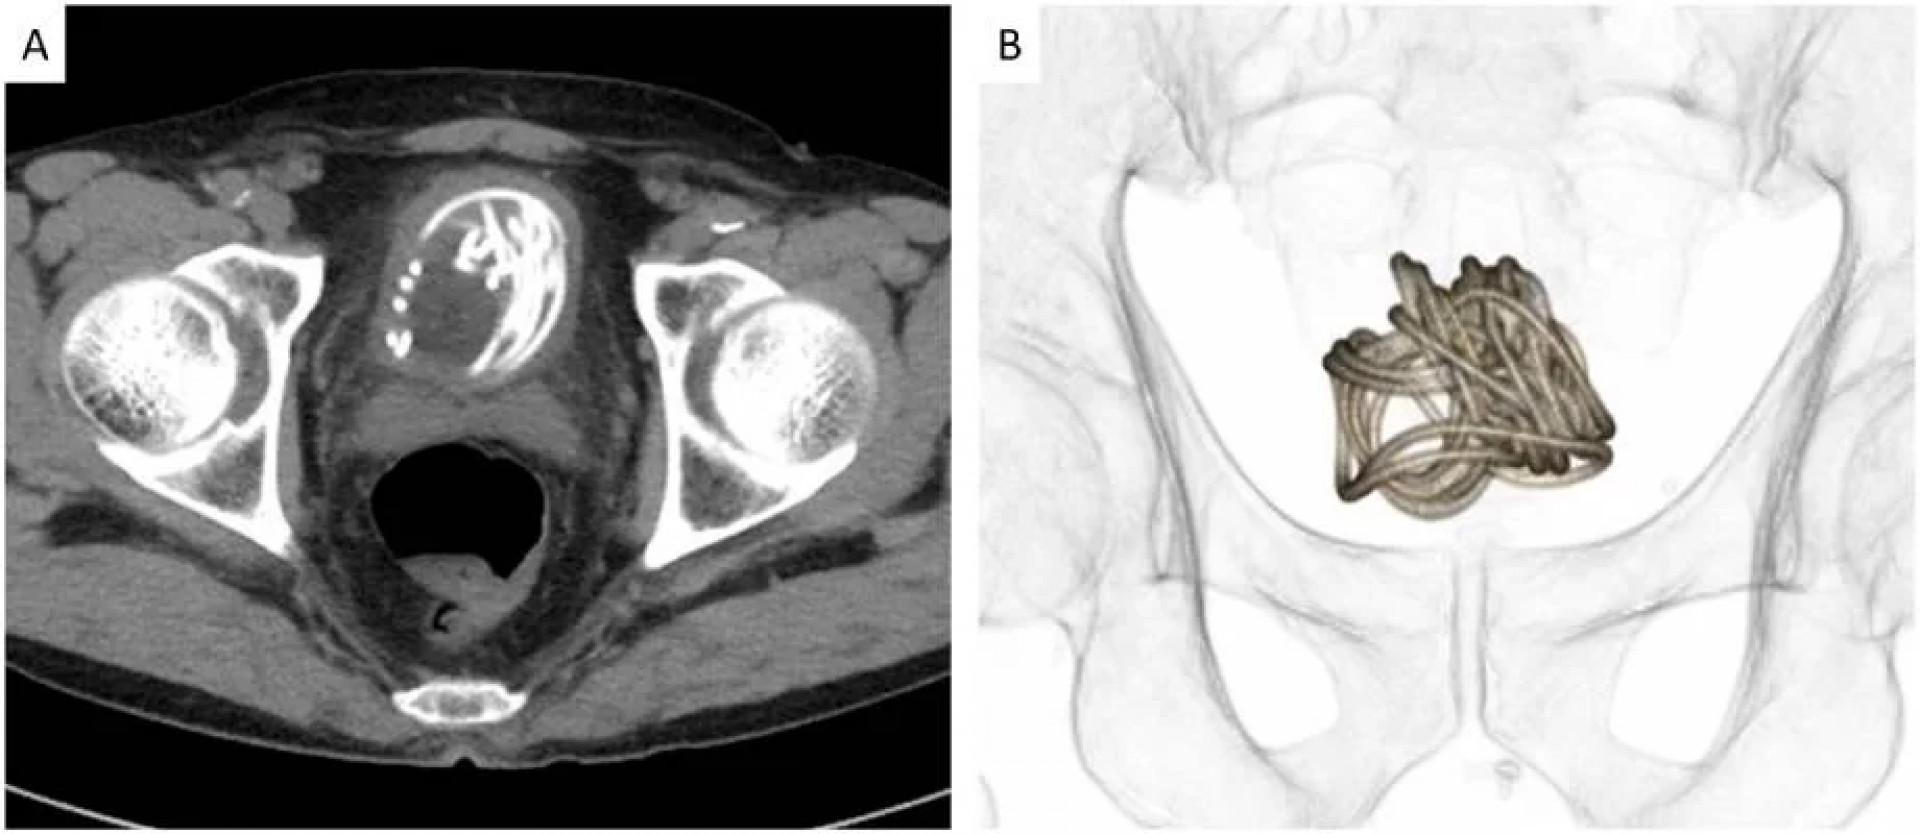

“Primeiro realizamos um ultrassom e identificamos um objeto grande na bexiga do paciente. Depois fizemos um raio-x, que revelou um corpo estranho enrolado em forma de fio", detalhou Toshiki Kijima, autor do relatório publicado na revista médica.

Depois do exame, a equipe fez uma tomografia do paciente para escolher o melhor jeito de tirar a corda. "Usamos um programa de computador em 3D para nos direcionar pois percebemos que seria impossível puxar a corda pelo pênis”, afirma Toshiki.